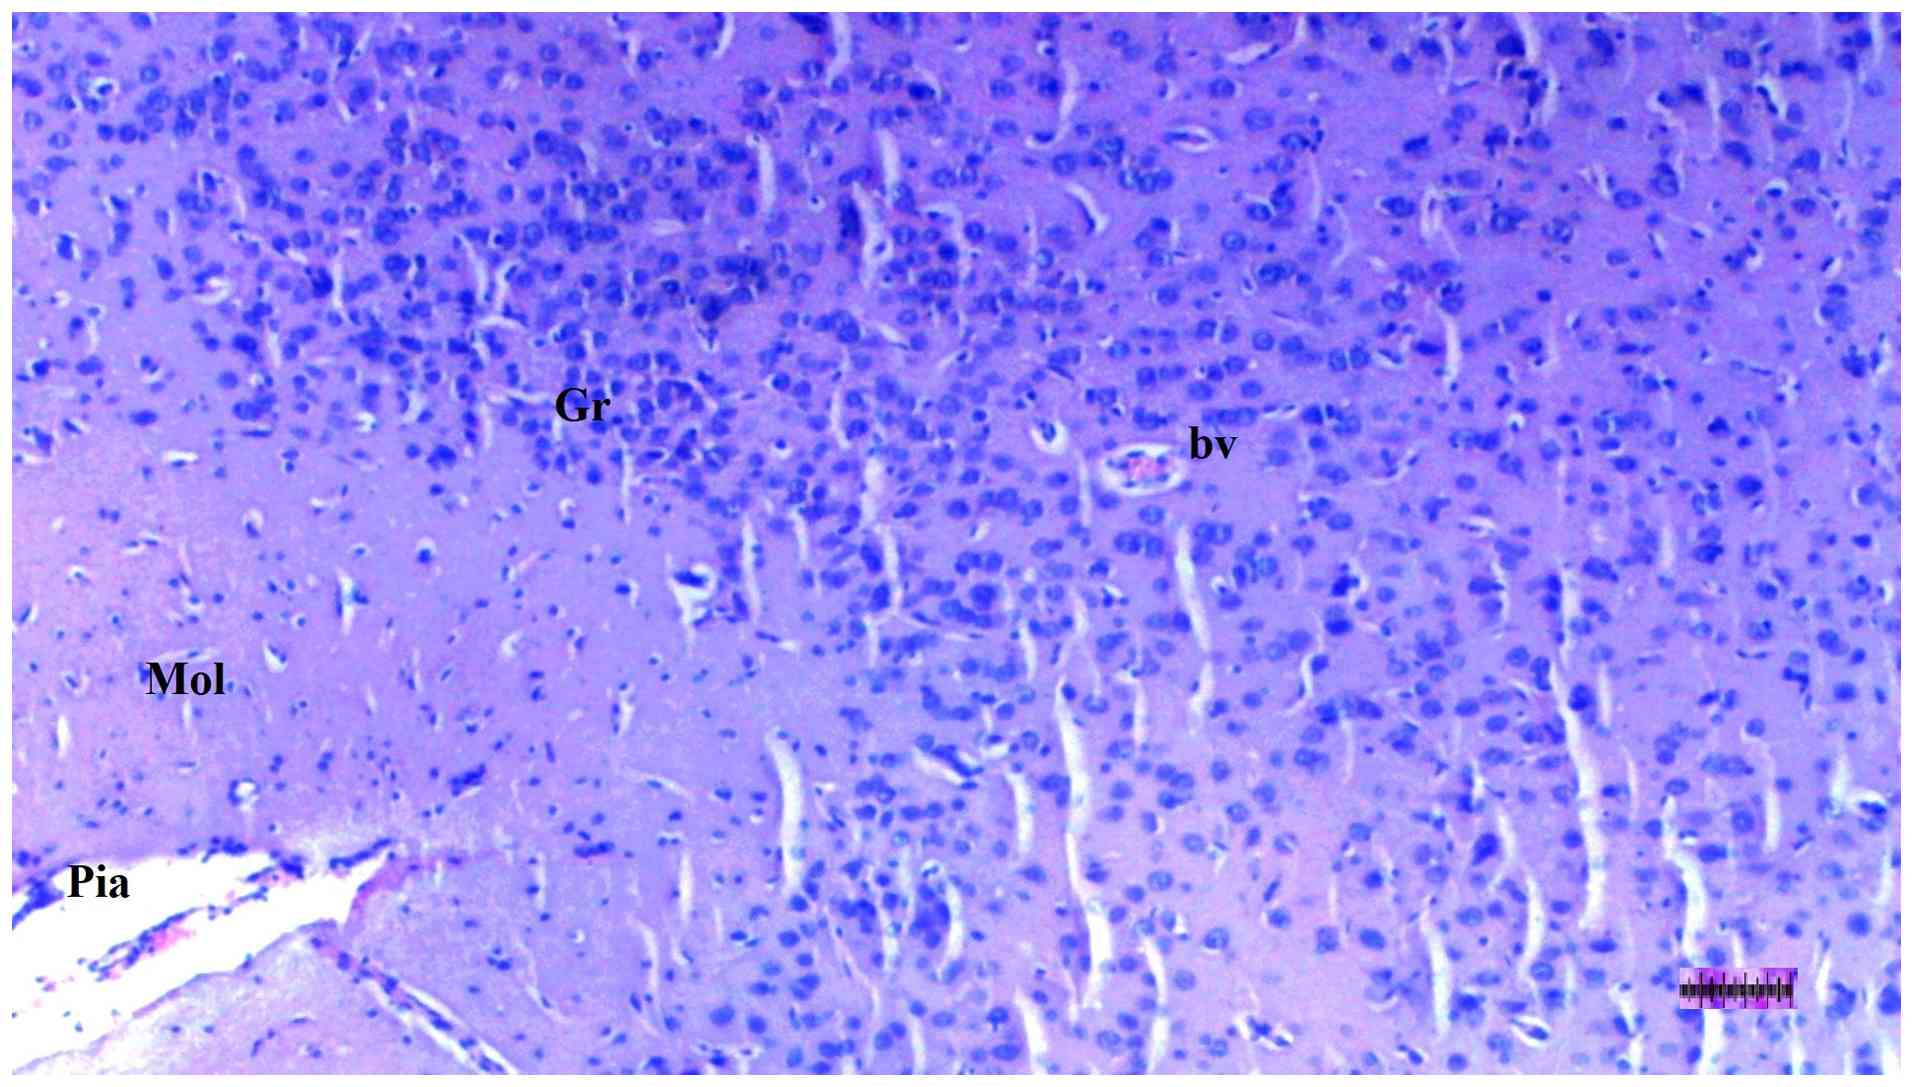

Representative light microscopy of

brain tissue from the diabetes + sepsis + fullerenol C60

group. H&E staining. Magnification, x40. Mol, molecular layer;

Gr, granular layer; Pia, pia matter; bv, blood vessels.

Figure 12

Representative light microscopy of brain tissue from the diabetes + sepsis + fullerenol C60 group. H&E staining. Magnification, x40. Mol, molecular layer; Gr, granular layer; Pia, pia matter; bv, blood vessels.

Histopathological examination of brain tissue

An increase in cellularity (macrophages and astrocytes) was found to be significantly different among groups (P=0.014). The DM/SEP group showed a greater cellularity compared with the S and D groups (P<0.001 and P=0.003, respectively), while the FUL/C-60 group exhibited significantly lower cellularity (macrophages and astrocytes) compared with the DM/SEP group (P=0.034) (Table III; Fig. 9, Fig. 10, Fig. 11 and Fig. 12). Inflammation, both macrophagic and astroglial, was significantly different among groups (P=0.036), being significantly more pronounced in the DM/SEP group compared with the S group (P=0.003).